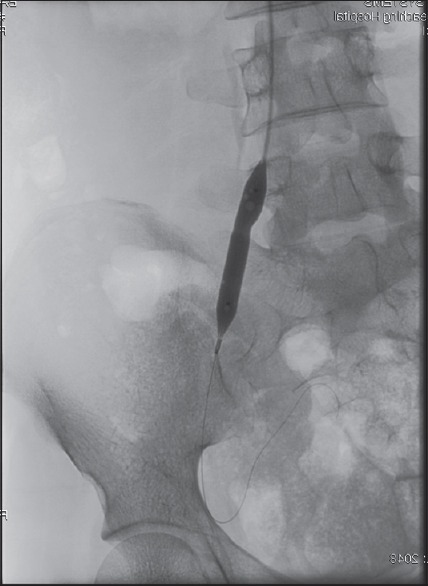

Materials and methods: We present our first 25 cases of peripheral angioplasty in Northwestern Nigeria. The clinical diagnosis of peripheral artery disease was confirmed with Doppler ultrasound and angiography. Angioplasty was done either through femoral or brachial artery approaches. The patients were monitored for minimum of 6 months with serial clinical and Doppler ultrasound examinations.

Results: Our patients consist of 19 males and 6 females. Their ages ranged from 20 to 80 years with a mean of 54 ± 17.5 years. There were 13 hypertensive and 15 diabetic patients while 5 patients have co-morbidities of diabetes and Hypertension. Although femoral antegrade route is the common access for angioplasty (14 out of 25), seven patients who were treated through the left brachial artery, six of them had either Type C or D aortoiliac disease in addition to distal lesions. At follow-up, 36% had limb amputation while one patient died a day after the procedure. Out of nine patients who had amputation, six are diabetic.